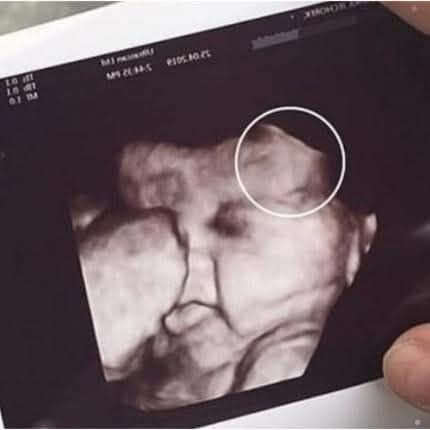

When 29-year-old Emily Foster, from Kent, England, arrived for her routine 20-week pregnancy scan, she expected the usual joy — a quick glimpse of her baby, a few happy tears, and perhaps a keepsake photo. But halfway through the scan, the technician suddenly laughed.

“Is that… hair?” she asked in disbelief.

On the black-and-white monitor, Emily’s unborn daughter already appeared to have a fuzzy halo around her head. Even the doctor joined in the laughter: “Looks like you’ve got a little rock star in there!” Neither of them could have guessed just how true that prediction would be.